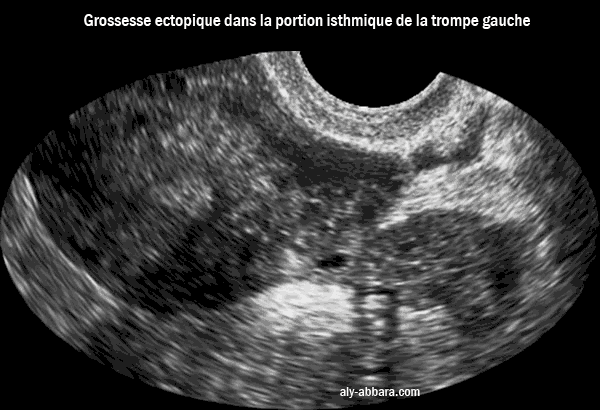

Grossesse extra-utérine dans la portion isthmique de la trompe

Il s'agissait d'une grossesse ectopique en près rupture et à l'origine d'intenses douleurs pelvienne, avec un dosage de hCG plasmatique faible, seulement 65 UI/litre)

Grossesse extra-utérine tubaire isthmique